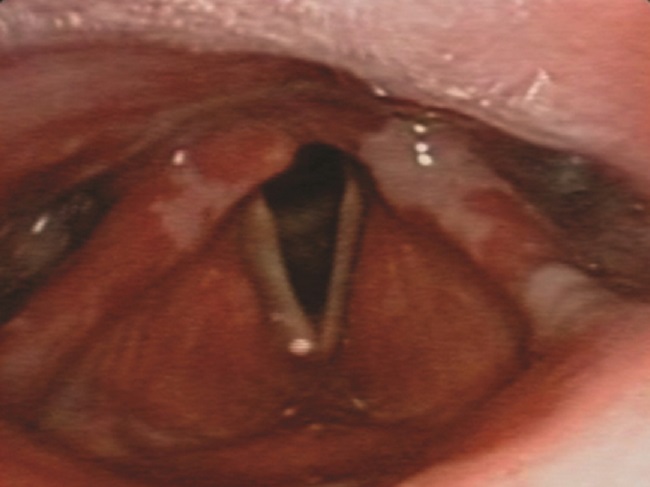

Se decidió aumentar la prednisona a 50 mg/día vía oral y se completaron siete días con cefotaxima. Se realizó endoscopia nasofaríngea, demostrándose mucositis amplia de cavidad oral, con extensión a faringe y laringe, sin compromiso de mucosa nasal (figura 2). Además, se tomó biopsia de la mucosa del labio inferior y glándula salival, en la que se registró mucosa ulcerada sin epitelio valorable, con sialoadenitis crónica.